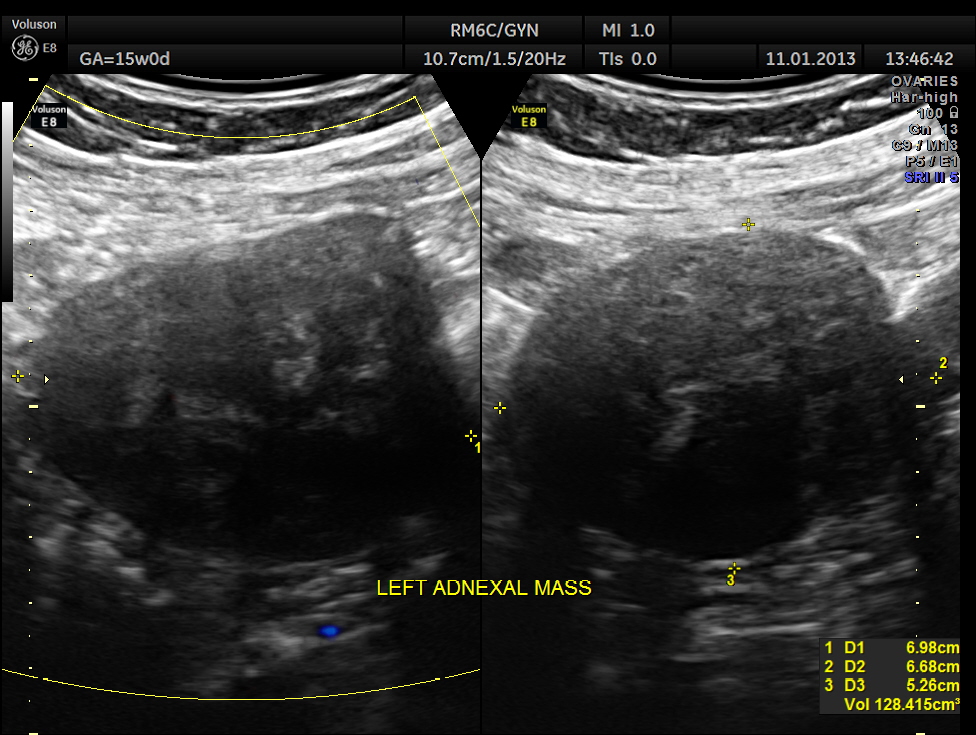

This was a 28 year old lady , primi gravida , who presented with acute lower abdominal pain . Her gestational age was around 15 to 16 weeks.

Left adnexal solid mass was seen.

So this patient was taken up for surgery because of the clinical presentation of acute pain , probably torsion. The mass lesion was removed and the pathologist reported it as PARA OVARIAN FIBROMA . The pregnancy was continued normally and was uneventful . The fetus showed mild bilateral pelvi ectasis persistently from 28 weeks onwards till delivery. Scan done 1 month after delivery showed normal kidneys in the child.